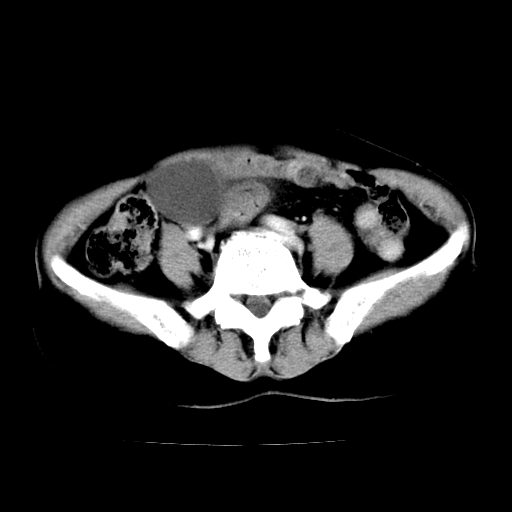

标题: CT24785:女,62岁,发现下腹部肿物半年。 [打印本页]

标题: CT24785:女,62岁,发现下腹部肿物半年。

女,62岁,发现下腹部肿物半年,下腹部不适。

老年女性患者,盆腔囊实性占位,ct增强不均匀强化,未见壁结节,未见腹水及盆腔积液,考虑附件囊腺瘤可能性大!